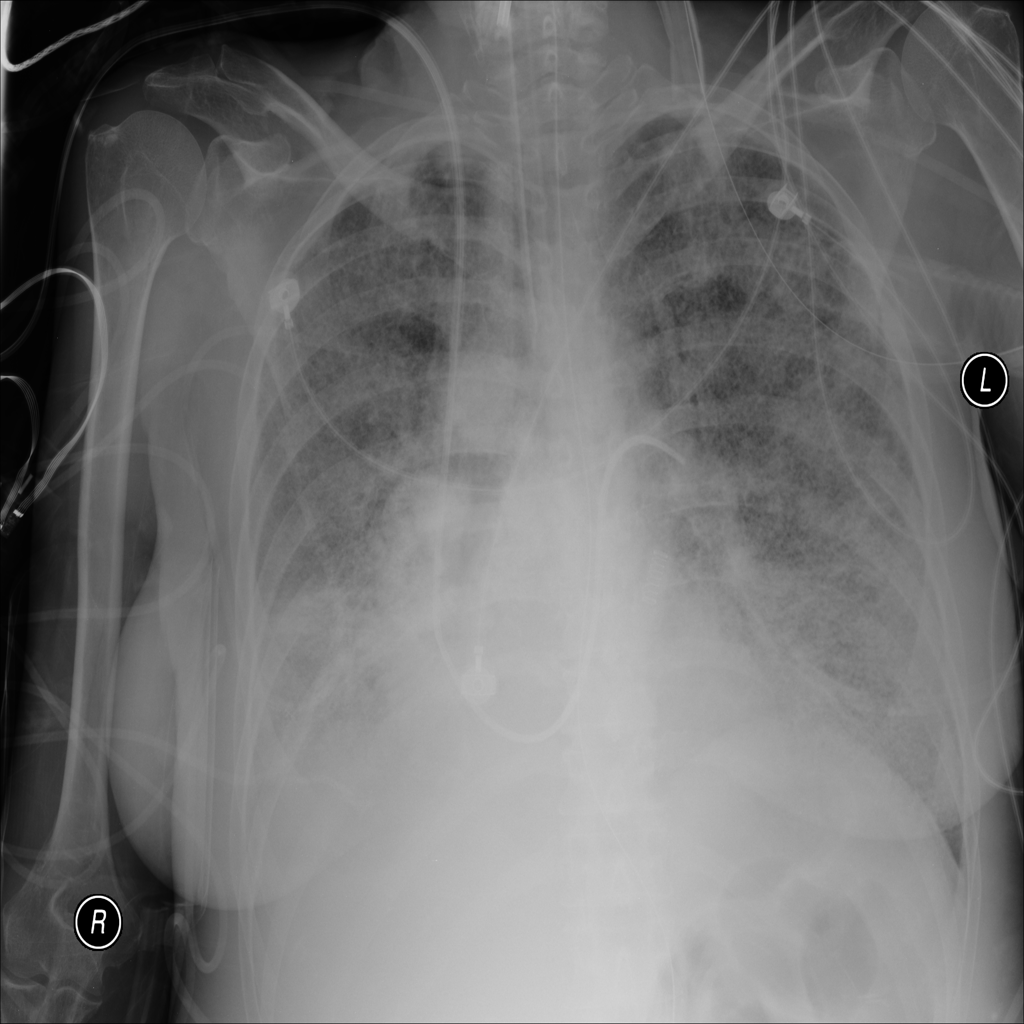

PAT-B733 · IMG-000Consolidation

PAT-B733 · IMG-000

PA